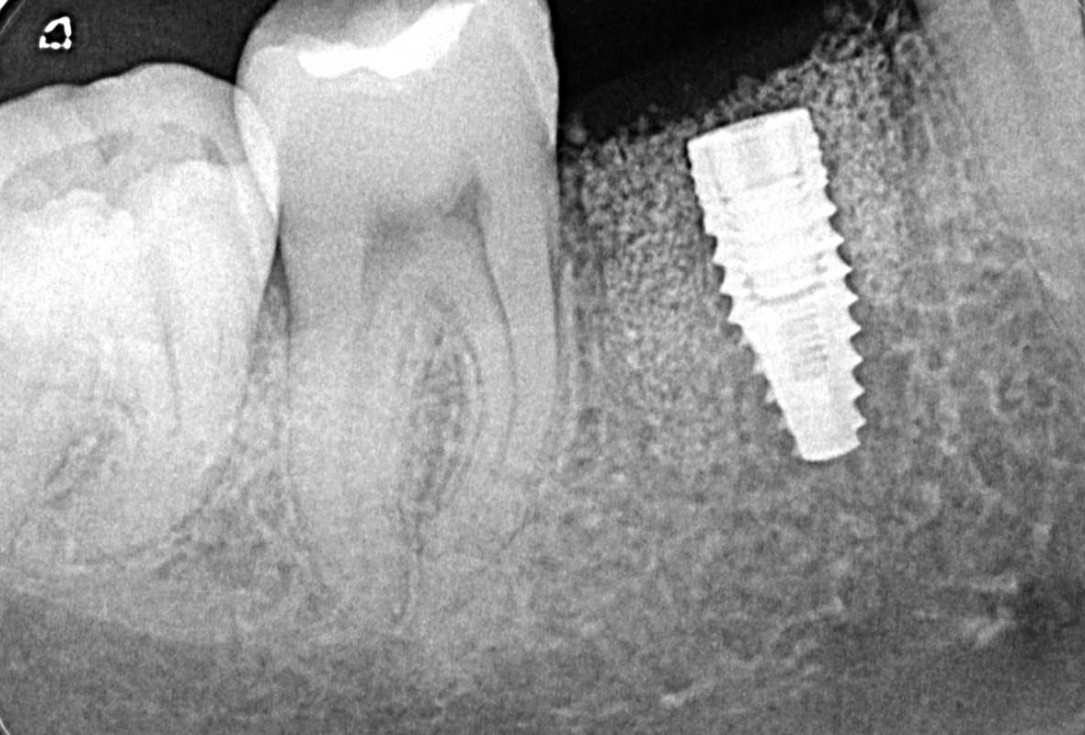

02/25 - Planning of an implant supported restoration of tooth 46Immediate implant placement and peri-implant bone augmentation with cerabone® plus - Dr. R. Block Veras